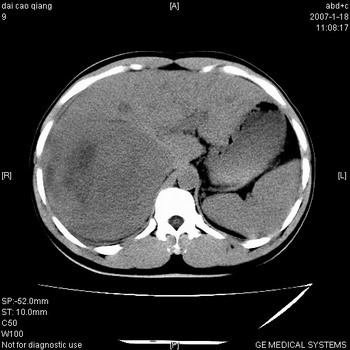

符合巨块型肝癌表现:

1、平扫低密度,增强后表现为快进快出。

2、动脉期可见迂曲的动脉供血血管

3、并可见门静脉右支癌栓形成

4、可见假包膜

5、腹主动脉旁结节影,考虑肿大淋巴结。

肝右叶巨大不均匀低密度肿块,前缘有假包膜,增强明显的呈快进快出表现,门脉右支有癌栓,病人虽然年轻但还是首先考虑肝右叶巨块形肝癌,病人血象高只能说有合并感染。不支持肝脓肿。